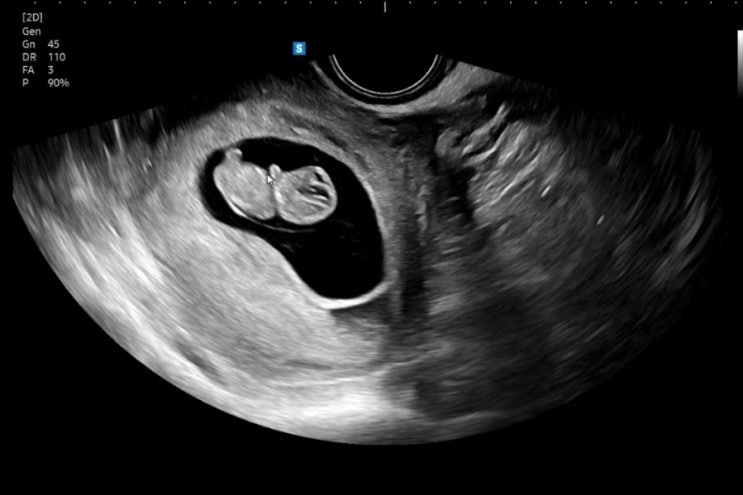

15주5일, 임산부 일상 ㅋ.ㅋ 성별확인

기나긴 시간이 흘렀따 입덧은 12주쯤 잠깐 좋아졌다가 13주에 다시 극악을 달리고 지금은 밤에만 속이 안좋...